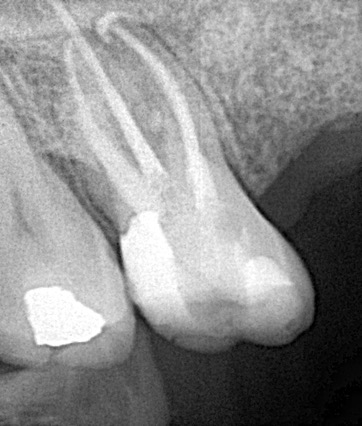

Retratamento Endodôntico

Em algumas situações é necessária a reintervenção endodôntica, ou seja, é preciso realizar um novo tratamento de canal.